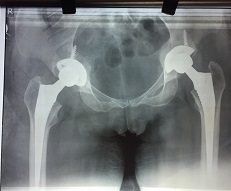

Preop AP View

Thr 25 Yea Male

Thr 25 Yea Male 4